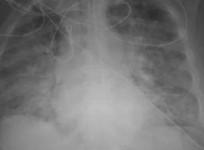

Covid shock: This image shows how coronavirus ravages lungs of unvaccinated people